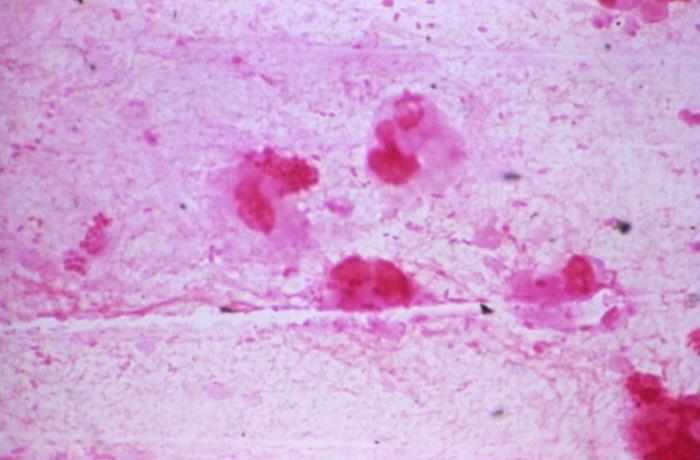

H influenzae

Trantracheal aspirate showing some Gram negative rods, but also Gram negative diplococci that were found in culture to be H. influenzae.

Source: CDC, Dr. Michael Miller